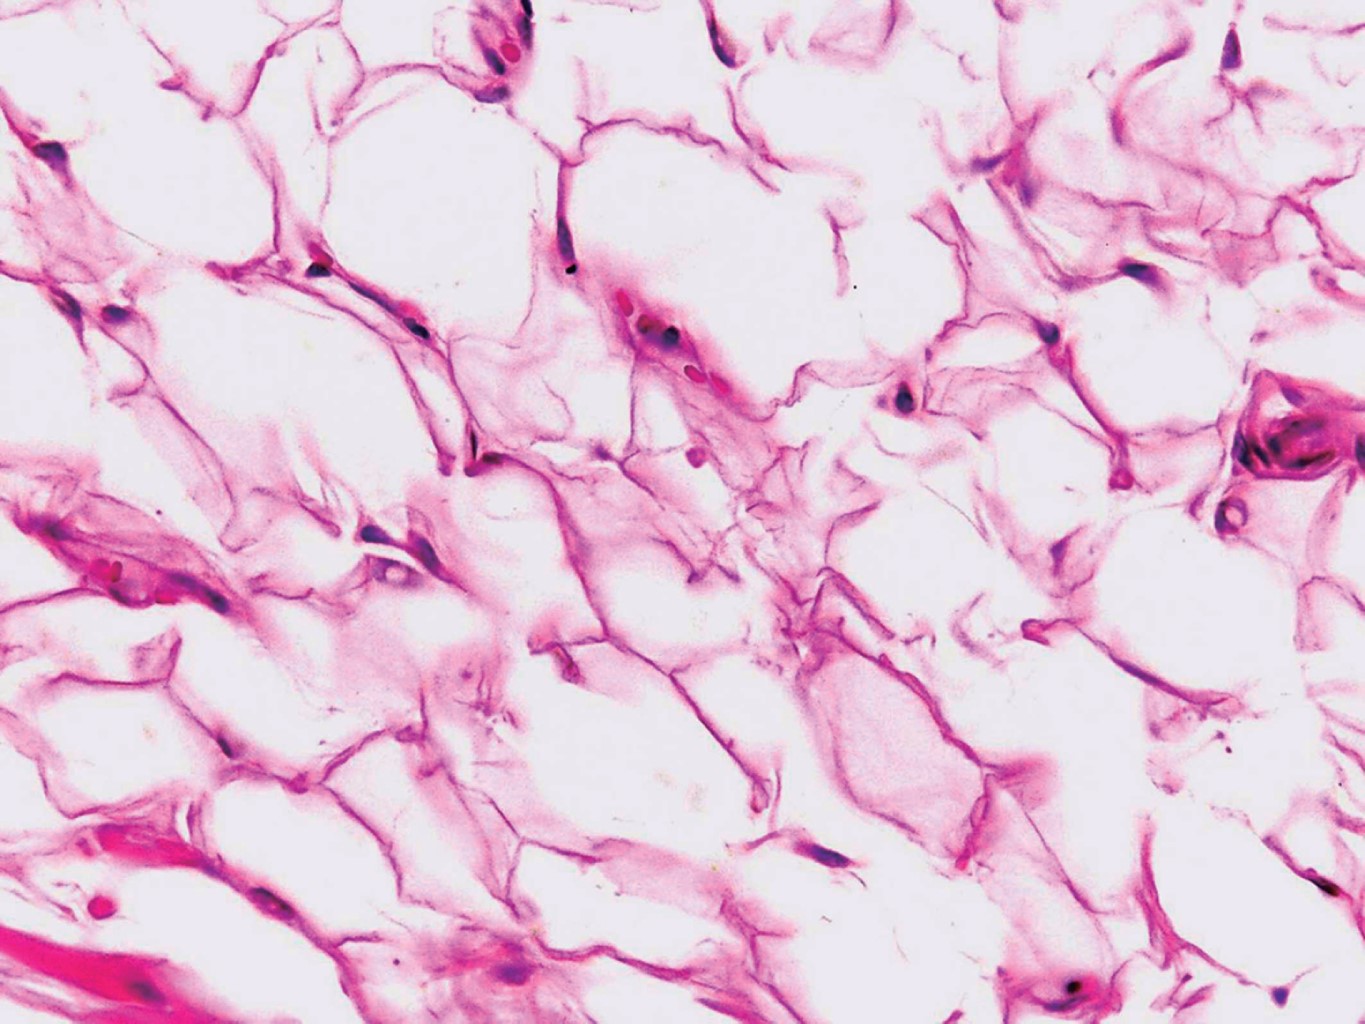

Con el diagnóstico presuntivo de lipoma en mucosa labial inferior, el paciente es referido al Servicio de Cirugía Dermatológica, en donde se realiza extirpación de la lesión con cierre directo (Figuras 2 y 3). El estudio histopatológico describe al corte la presencia de una neoformación bien circunscrita, constituida por numerosos adipocitos maduros de características normales, con algunos vasos dilatados y congestionados (Figuras 4, 5 y 6) confirmando con estos hallazgos el diagnóstico de lipoma. En el seguimiento postoperatorio del paciente únicamente se presenta cicatriz eutrófica; dos meses posteriores a la cirugía se da de alta.

Debido al lento crecimiento y evolución asintomática de estas neoformaciones, el diagnóstico suele retrasarse hasta que el tumor causa problemas funcionales o estéticos en los pacientes. Se calcula que el promedio de tiempo al momento de ser diagnosticado es de 2.6 años.5,7,8 El diagnóstico definitivo se establece mediante estudio histopatológico con tinción de rutina (hematoxilina y eosina), el cual muestra proliferación bien circunscrita de adipocitos maduros idénticos al tejido adiposo normal, aunque se ha reportado en algunos casos metaplasia cartilaginosa y ósea. En los lipomas intramusculares se pueden observar fibras de músculo estriado.9 Los lipomas, a diferencia del tejido adiposo normal, suelen estar bien circunscritos, en ocasiones encapsulados, pero sin vascularidad. Por otra parte, el tamaño de los adipocitos suele ser mayor en los lipomas, no obstante, la mayoría de las veces no es posible distinguir entre ambas entidades.10 En algunos casos puede haber hallazgos asociados a traumatismo o sobreinfección, como la presencia de infiltrado inflamatorio, necrosis o licuefacción grasa.4

Figura 5